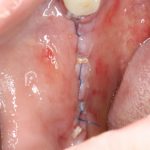

Результаты

Результат остеопластики методом остетотомии мы можем оценить уже через 4 месяца. Перед этим сделаем контрольные снимки (слева «до», справа «через 4 мес»):

Откроем область операции и посмотрим, что там:

Вроде как, всё неплохо. Наверное, можно поставить имплантаты?